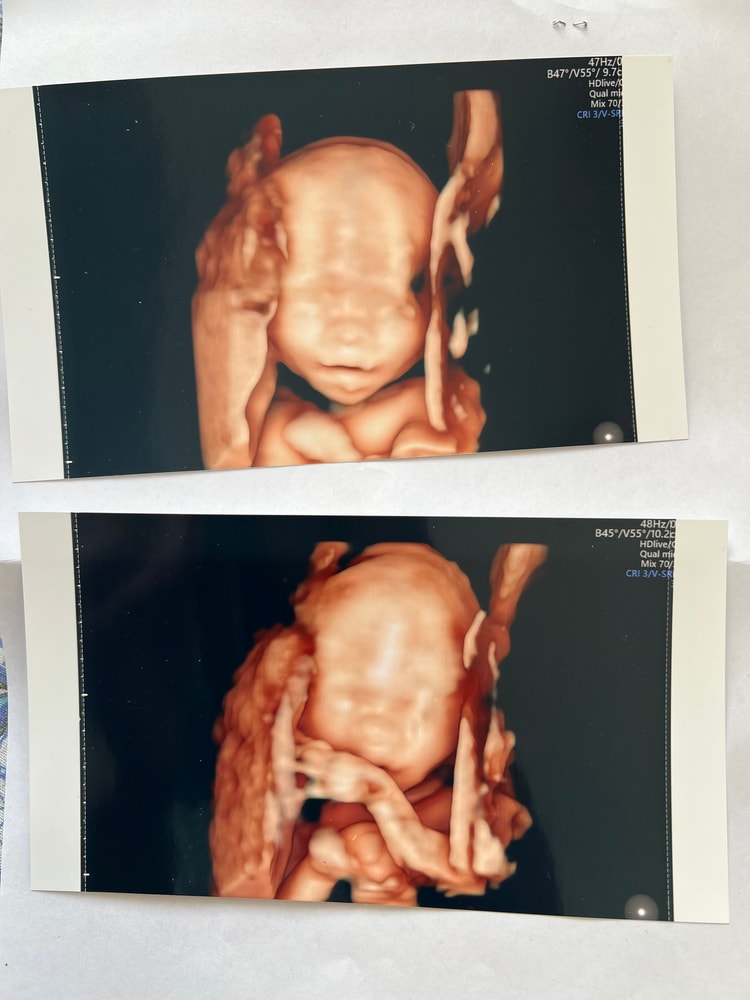

Деля , вот в 22 недели и в 30 примерно. Чем позже, чем интересней)) Изображение Изображение